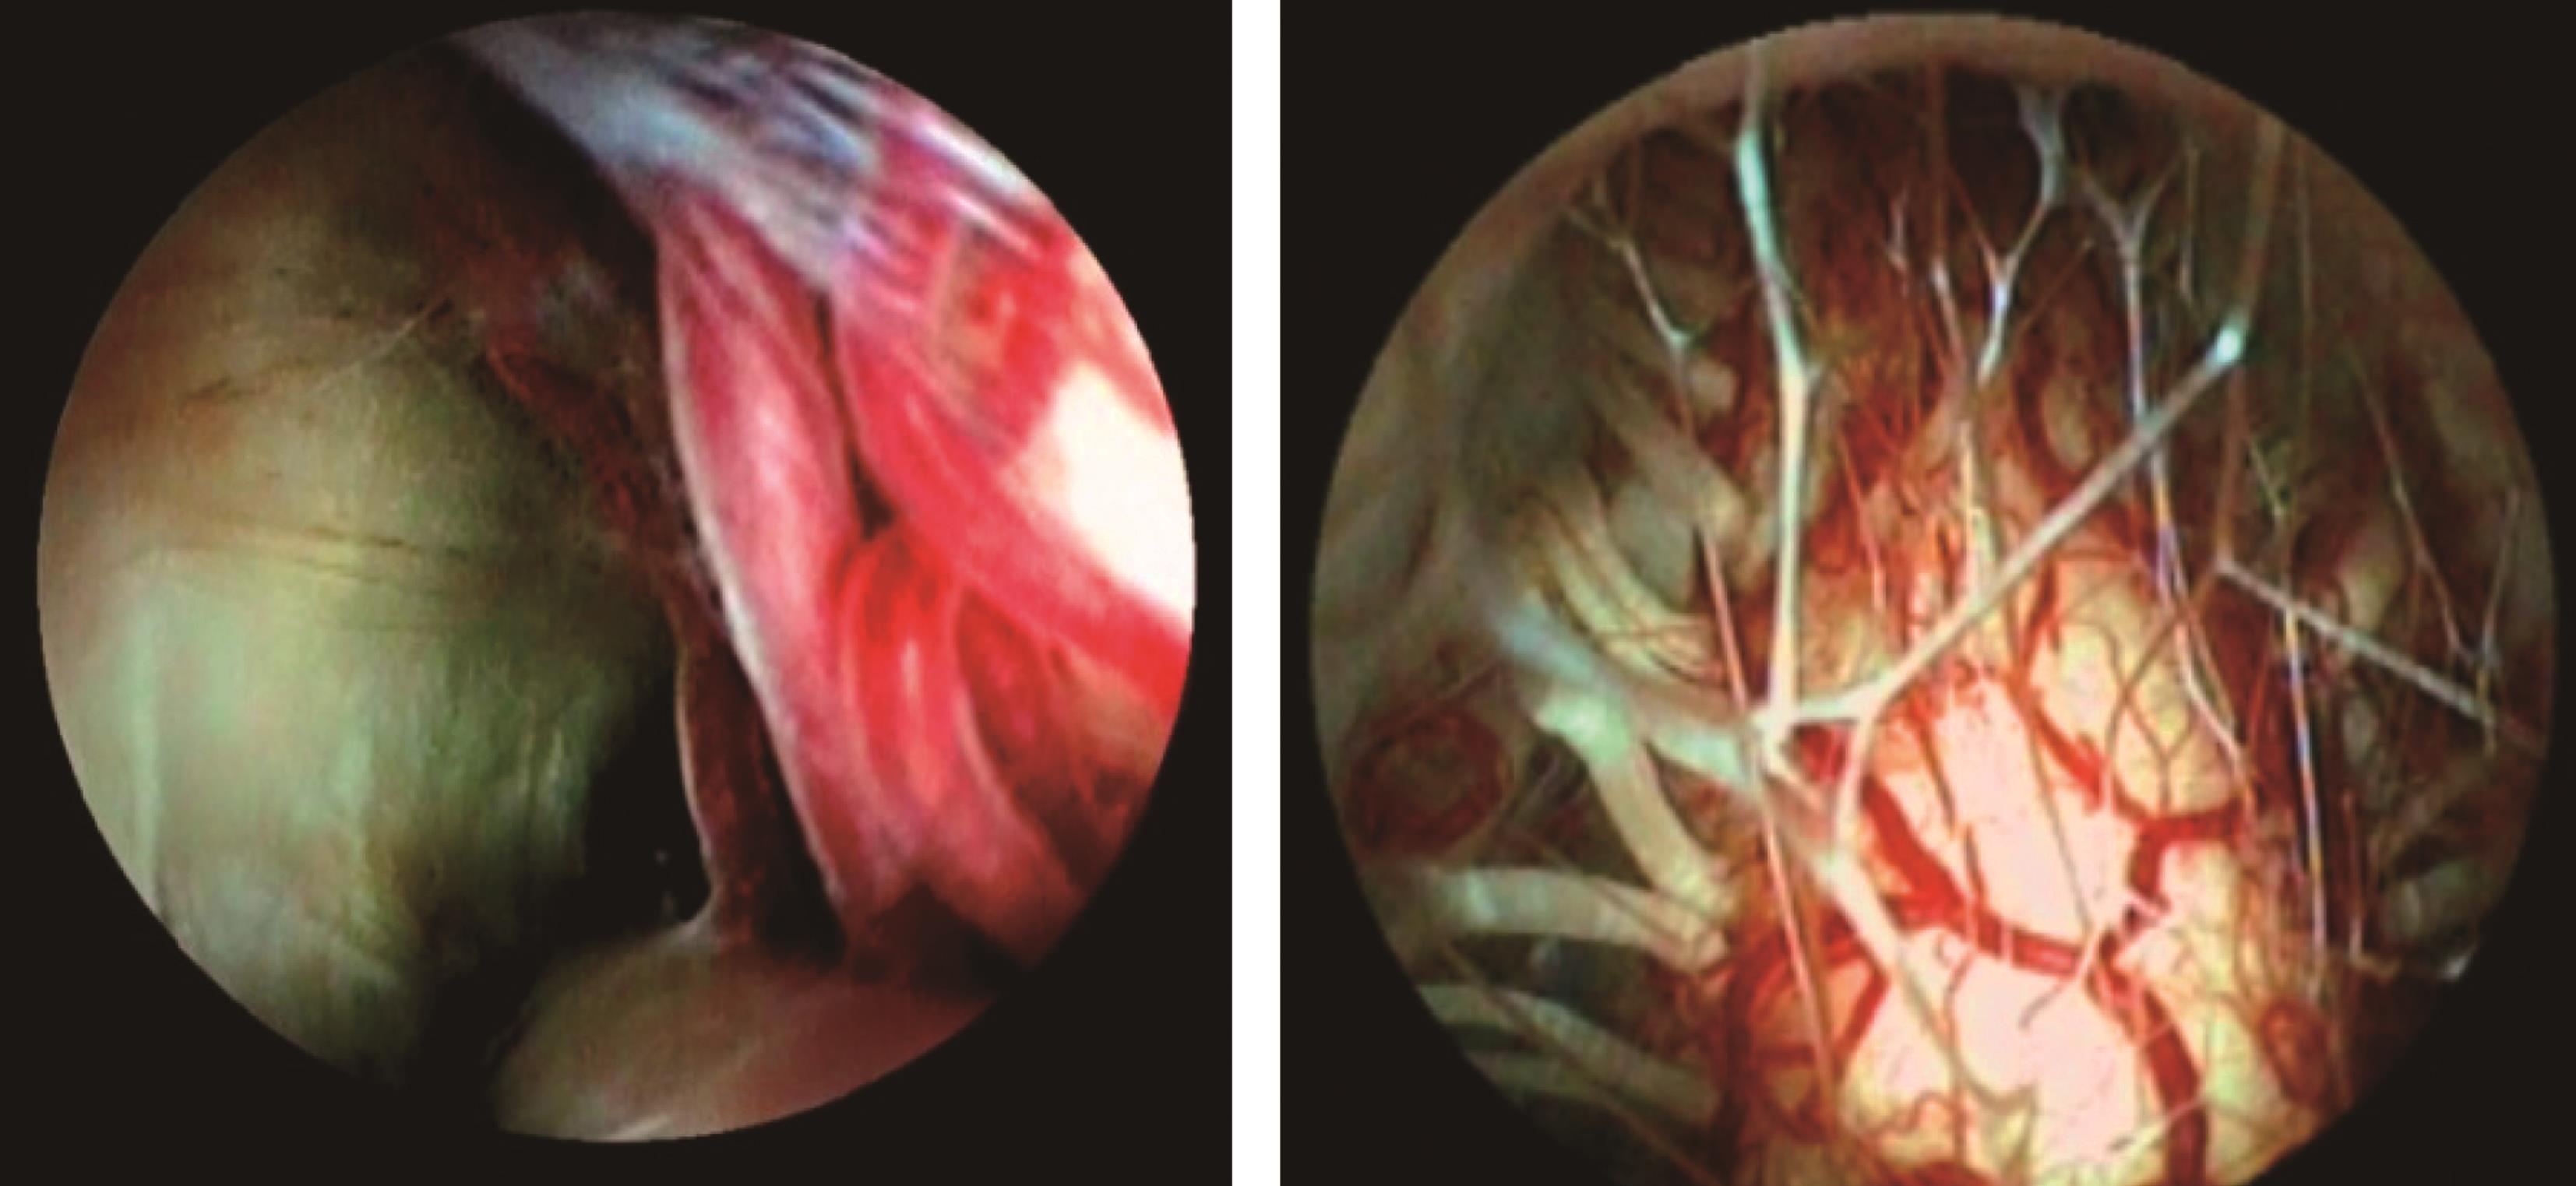

5.第三脑室造瘘 造瘘位置选在漏斗隐窝和乳头体之间的三角区,最薄弱的无血管处。先用内镜活检钳或单极电凝在第三脑室底进行穿刺,再用扩张球囊导管或活检钳置入穿刺孔(图3-1-3-4),扩大瘘口,通常瘘口直径不应小于5mm,以避免术后瘘口粘连闭塞。瘘口边缘少量渗血,可用双极电凝或电磁刀凝固止血。以37℃生理盐水或林格液冲洗瘘口,观察水流情况。检查下方的Liliequist膜,用同样方式打通该膜,以保证在镜下可清晰辨别基底动脉分叉和斜坡结构,确认瘘口通畅、与脚间池充分沟通。软性内镜下镜头可通过第三脑室底瘘口向下探查基底池直至枕大孔前缘(图3-1-3-5)。对第三脑室底造瘘困难或基底池粘连严重无法有效疏通者,在软性内镜下可探查终板,进行终板造瘘(图3-1-3-6)或第三脑室-小脑上池造瘘(图3-1-3-7)。

图3-1-3-5 软性内镜下探查基底池直

图3-1-3-6 软性内镜下探查终板进行

图3-1-3-7 软性内镜下行第三脑室